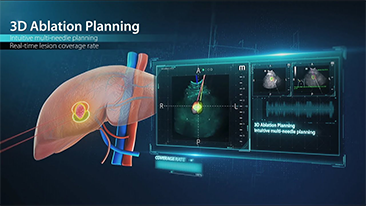

La gamme d'imagerie gÊnÊrale Resona de Mindray aide les cliniciens à obtenir des rÊsultats de diagnostic plus prÊcis et des traitements plus efficaces gr?ce à une gamme de sondes complète et à des outils cliniques avancÊs efficaces.